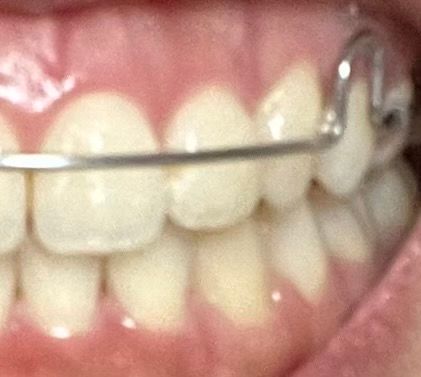

현재 느끼기에 씹는 힘도 약해져 있는 상황인데, 한번 깨끗하게 잇몸치료 받는게 좋은 상황일까요? 괜히 잇몸 건드리면 더 내려갈까봐 걱정되어 질문해봅니다ㅠㅠ + 제일 좋지 않은 잇몸쪽 사진 같이 올려둡니다

• 1번 째 사진